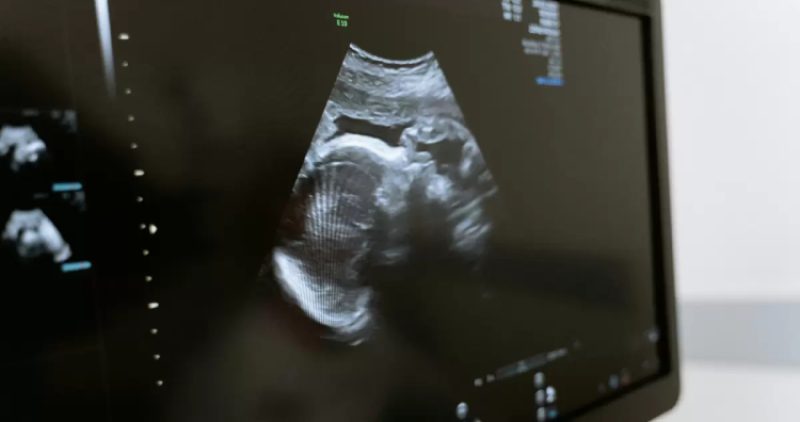

En el tercer trimestre de gestación, las participantes embarazadas se sometieron a una neurosonografía transvaginal, una ecografía avanzada que permite examinar con detalle la morfología y las estructuras del cerebro fetal.